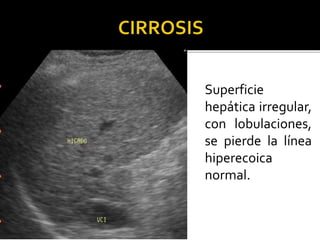

Superficie

hepática irregular,

con lobulaciones,

se pierde la línea

hiperecoica

normal.

 Ausencia de la delgada capsula.

 Disminución de los vasos periféricos.

 Angulo abierto enV. hepáticas. Mayor 45º

 Aumento del calibre de la porta.

 Nódulos de regeneración con desplazamiento

vascular.